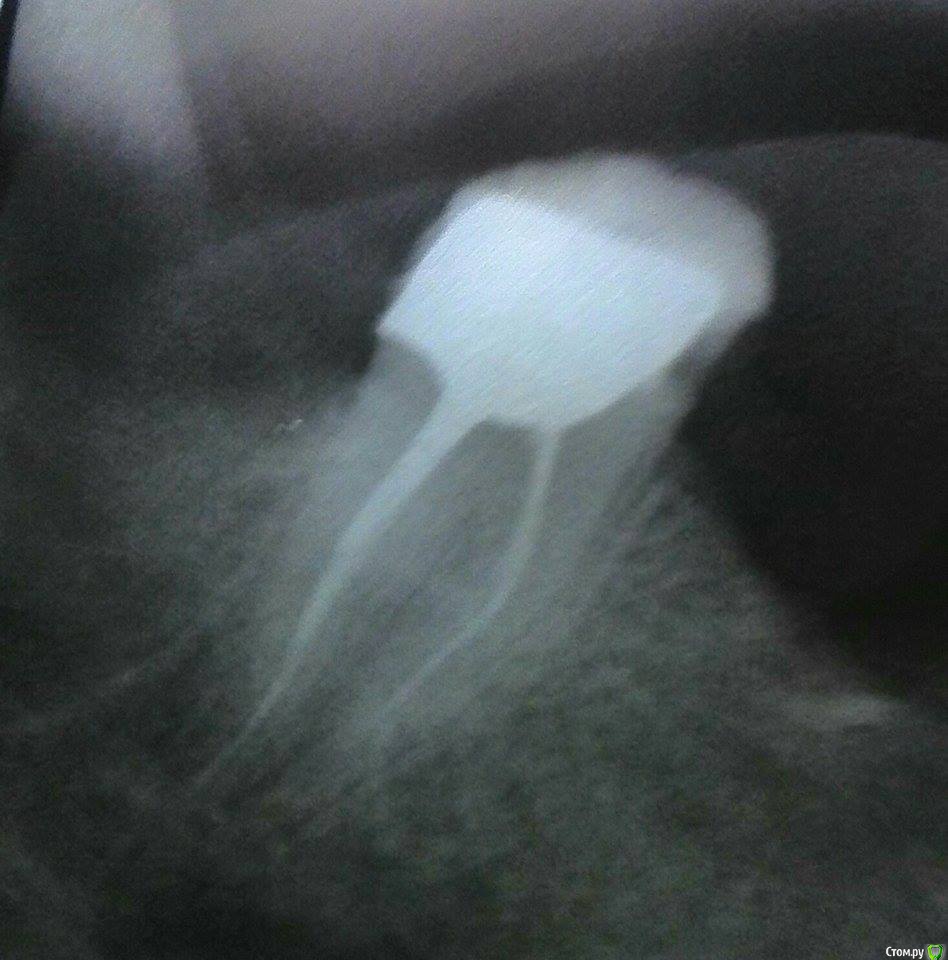

Jonatan Опубликовано 18 декабря, 2014 Автор Поделиться Опубликовано 18 декабря, 2014 (изменено) Вот. Сфотала, пока несла в кабинет - не выдают там снимки. Вроде бы ничего страшного, вкладка вдоль канала. Но боль есть, десна со стороны удаленной 8-ки иногда дает болевые импульсы (жжение, нытье), 7-ку ломит, как кости от ледяной воды, от горячего, холодного. Сейчас поняла, что так же, но куда сильнее и постоянно (с иррадиацией в верхнюю 6-ку) болело сразу после удаления 8-ки (рядом с этой вот 7-кой). Само удаление было моментальным и безболезненным, и лунка почти не болела, а вот 7-ка эта болела страшно, 3 недели на кетанове. И потом боль локализовалась вот в этом месте, там как будто так и не зажила слизистая, странно болит, касание зубочисткой как удар током. С удаления 8-ки 2.5 месяца прошло . Изменено 18 декабря, 2014 пользователем Jonatan Ссылка на комментарий

SDC Опубликовано 18 декабря, 2014 Поделиться Опубликовано 18 декабря, 2014 Вот. Сфотала, пока несла в кабинет - не выдают там снимки. Вроде бы ничего страшного, вкладка вдоль канала. Плохо сфотографировали. Надо было спрятать в карман снимок. Дошли до кабинета - упс, потеряла )))Воспаление периодонта - периодонтит 7-го зуба. Ссылка на комментарий

Jonatan Опубликовано 18 декабря, 2014 Автор Поделиться Опубликовано 18 декабря, 2014 Так зуб совсем не болит при накусывании, настукивании, в покое, ночью и т.д.Неделей раньше снимали проверить как каналы пройдены - там все было без теней у верхушек, чисто.Мне кажется, периодонтит с виду из-за как всегда плохого ракурса (еще и тень падает).Постоянно свербит десна и болит на температуру - ломит. Ссылка на комментарий